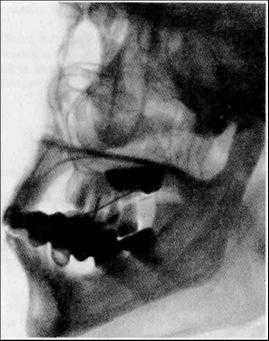

Рентгенографию тела и ветви нижней челюсти в боковой проекции проводят на дентальном рентгенодиагностическом аппарате.

Проводится также и боковая панорамная томография, на боковом панорамном снимке одновременно отображаются зубы верхнего и нижнего ряда каждой половины челюсти.